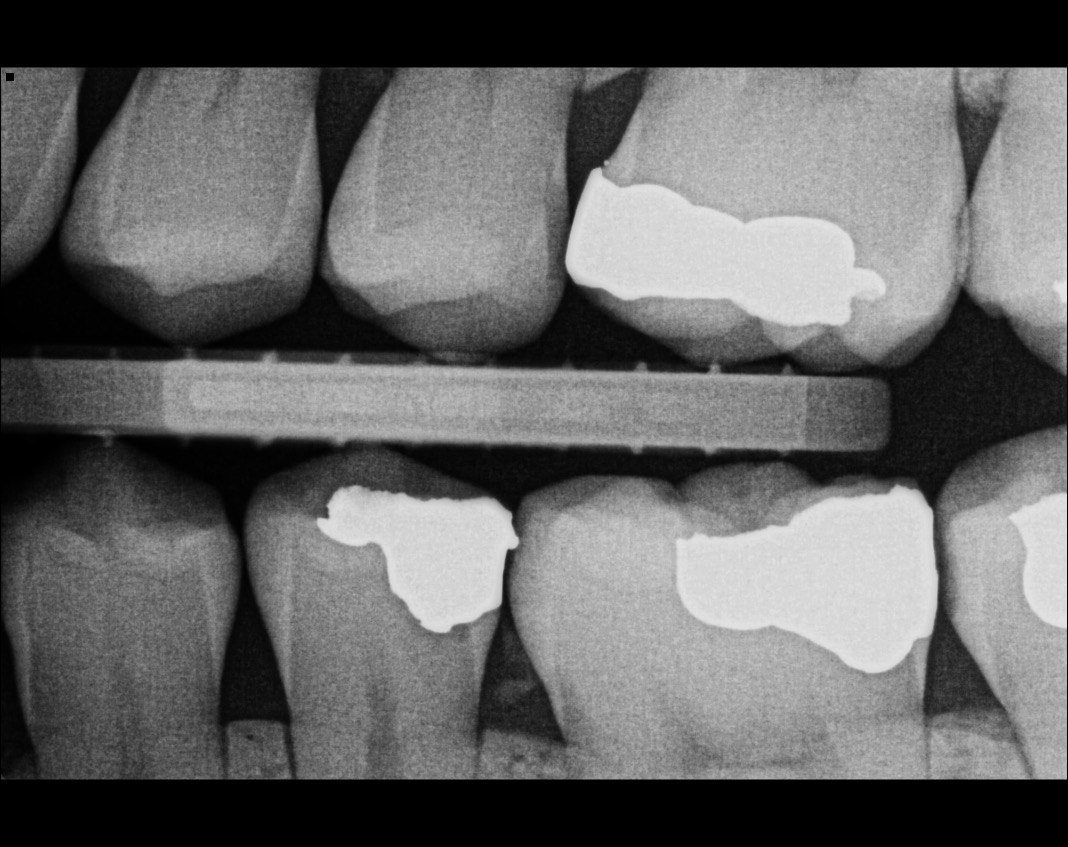

Question 11: Which materials cannot be seen in the print of the X ray?

Question 12: What option cannot be selected for the following X ray?

Question 13: What option cannot be selected for the following X ray?

Question 14: Which surface shows overhang restoration?

Question 15: Which surface shows overhang in the restoration?

Question 16: Which surface shows overhang?

Question 17: Which surface shows overhang?

Question 18: Which surface shows overhang?

Question 19: Which option can be chosen for the tooth # 3.6?

Question 20: which tooth shows defective resotration?